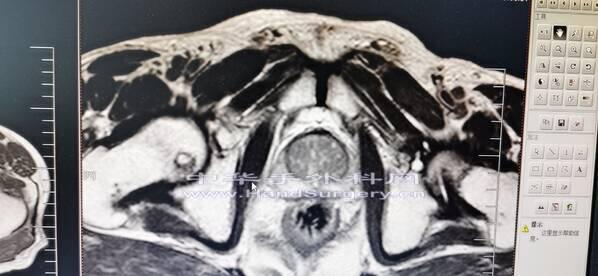

肛肠肿瘤患者,行盆腔核磁检查无意间发现股骨头肿物

囊肿影像局限,孤立,不在负重区,暂不考虑骨坏死。

会诊意见:考虑孤立性骨囊肿,不除外转移